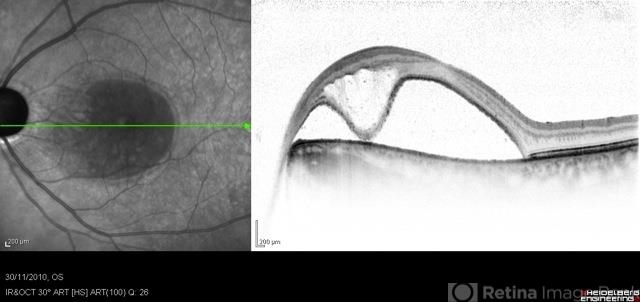

- optic pit, maculopathy, glaucoma

Optical coherence tomography system

Heidelberg Spectralis - Description

- Optical coherence tomography of the left eye of a 60-year-old man with an acquired optic pit maculopathy and glaucoma. The image shows subretinal fluid extending to the optic nerve and schisis of the outer retinal layers.